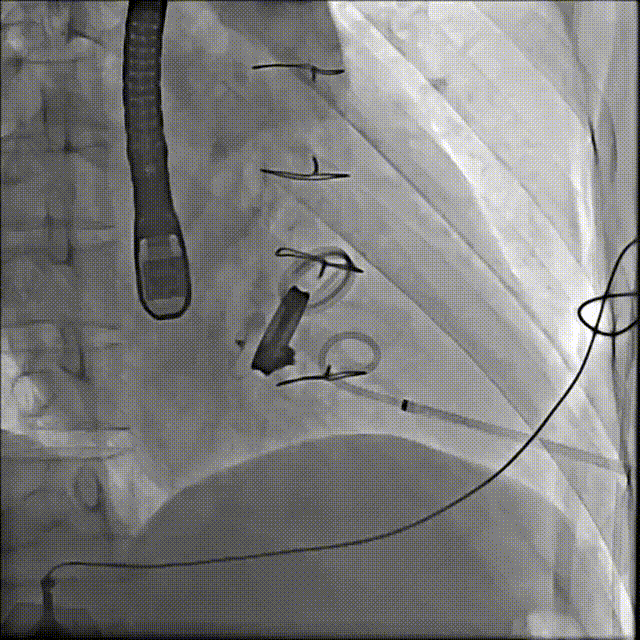

手术操作

1.患者平卧位,食道超声检查瓣周漏位置及大小,并引导穿刺心尖,选择7F鞘管通过10点位置瓣周漏口,将单弯导管送入左心室,置换超硬导丝至左心室,选择12-14mmPDAO封堵10点位漏口。

3.选择7F鞘管通过1-2点位置瓣周漏,彩超显示鞘管对瓣周漏口的影响较小,结合漏口大小,选择14-16mmPDAO封堵此处漏口。

术后封堵器形态位置